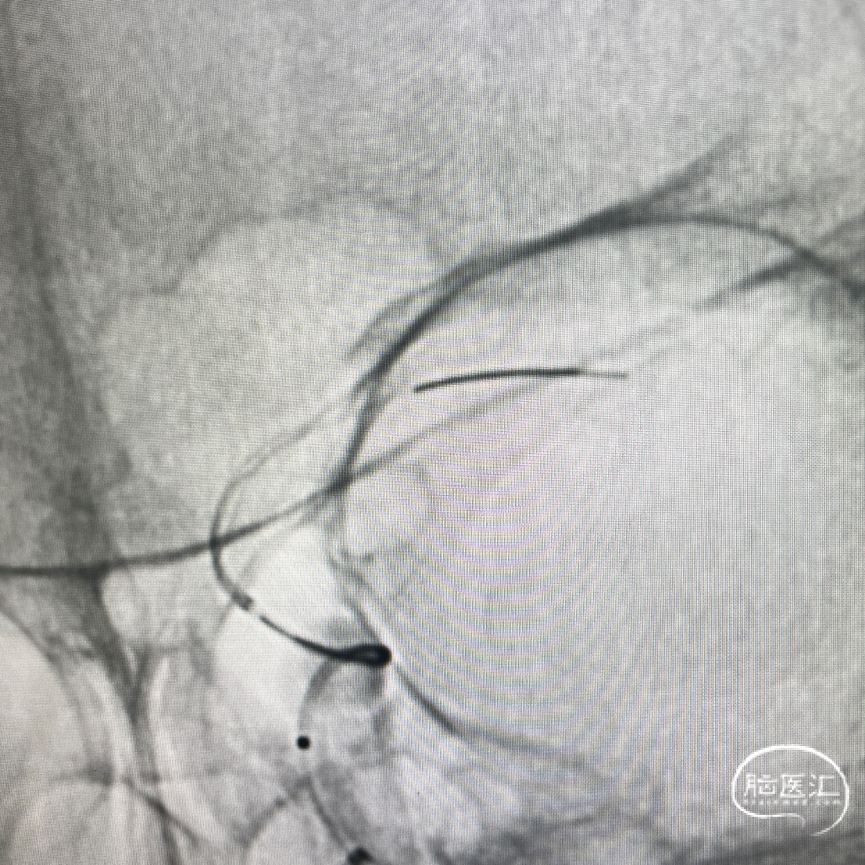

将泰杰Frepass® TJMC18Plus 支架微导管超选至左侧MCA,沿着微导管顺利输送泰杰Nuva®血流导向密网支架TJED-D-6.0-16到位,头端定位。

继续推拉结合,释放支架。

完全释放支架后导丝按摩,进一步增加贴壁效果。

术后DSA即刻造影见Nuva®血流导向密网支架远近端均定位准确,贴壁良好。